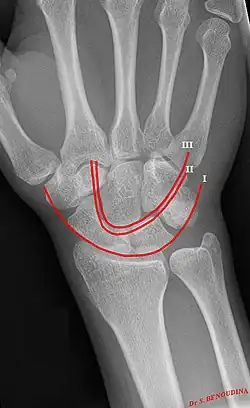

Gilula carpal arcs.

Gilula's lines are three arcs drawn on an AP radiograph of the wrist used to assess the alignment of the carpal bones.[1] They were first described by Louis A. Gilula in 1979.[2]

There should be no step-off in the contour of the lines when drawn on a normal wrist.

First arc running along the proximal convexity of the scaphoid, lunate and triquetrum

Second arc running along the distal concavities of the scaphoid, lunate and triquetrum

Third arc running along the proximal curvatures of the capitate and hamate